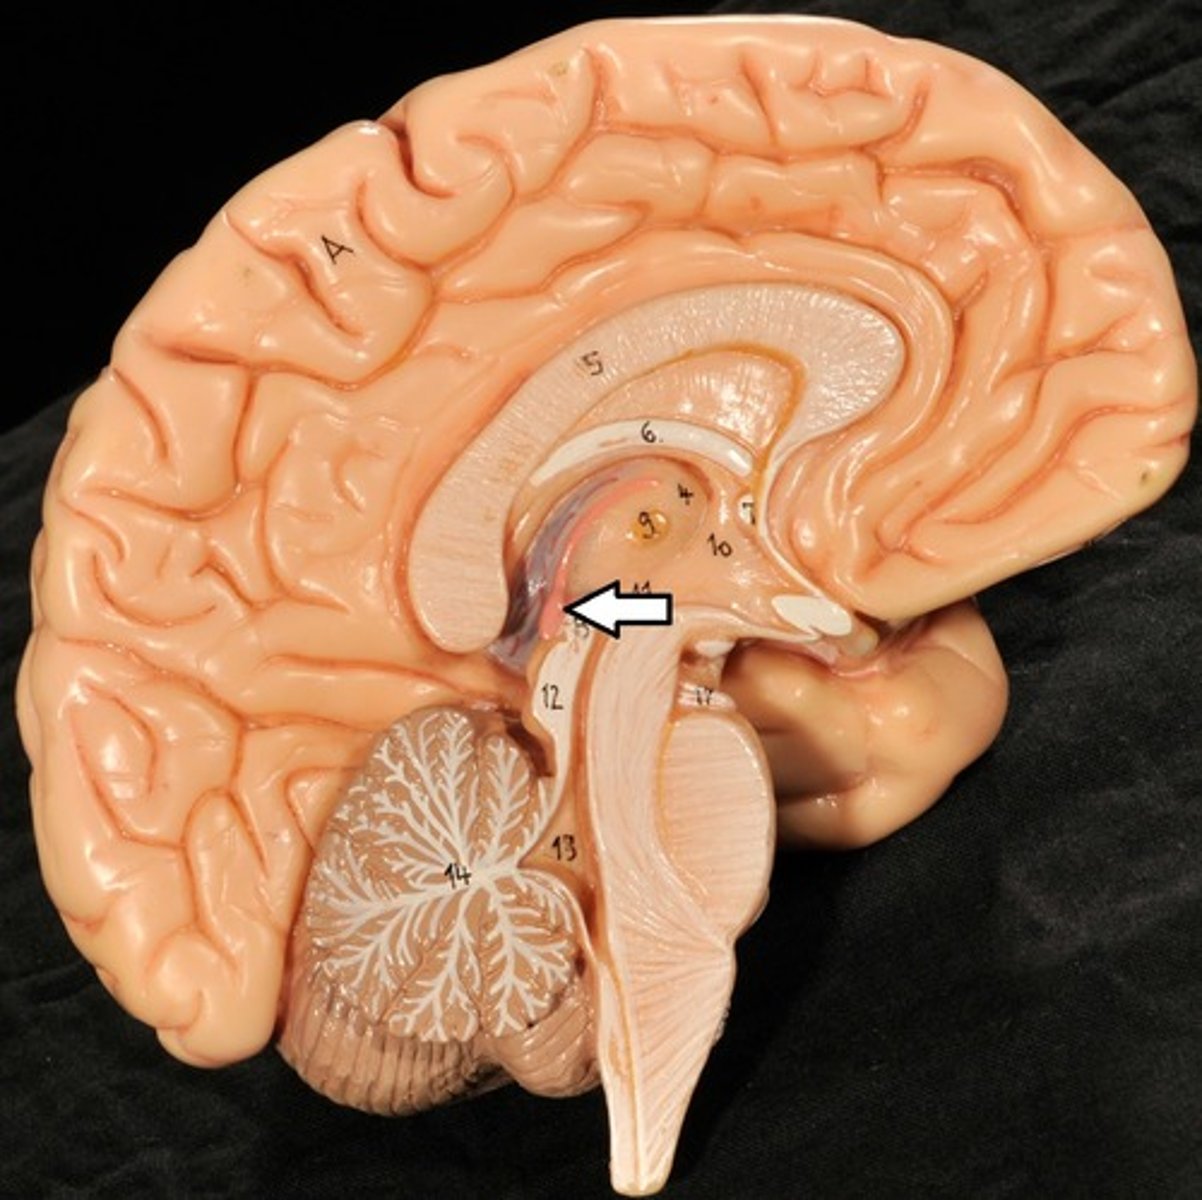

Ventricles

1) Right & left lateral ventricles:

-Anterior, Posterior & inferior horns

2) 3rd Ventricle, Cerebral aqueduct, 4th ventricles

4) Apertures (Narrow openings) into subarachnoid space of spinal cord

Anterior Horns

Posterior Horns

Inferior Horns

3rd Ventricle

4th Ventricle